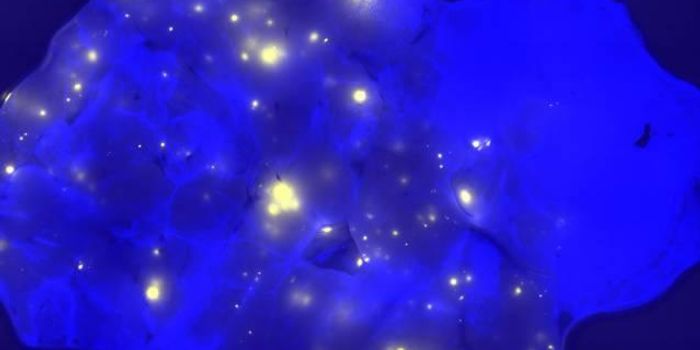

Follow a curation of discoveries and updates in immunology focusing on immune responses to infectious disease, structure and function, and developments in the defense against infection.